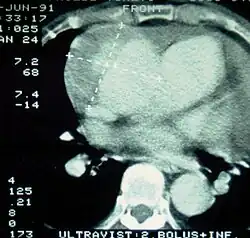

|

| Computed tomography (CT) | Legend |

| Disección aórtica tipo A de Stanford 1 aorta ascendente, cierto Lumen - 2 Lumen falsa - 3 arteria pulmonar 4 aorta torácica descendente - 5 vértebra torácica | |

La Angiografía de Tórax por Tomografía Computarizada (Angio-TC de Tórax) es una prueba no invasiva de rápido acceso cuyo objetivo es dar una vista tridimensional de la aorta. Estas imágenes son producidas rápidamente, teniendo que cortar rebanadas delgadas del pecho y el abdomen, combinados en el ordenador para crear la sección transversal. A fin de delinear la aorta a la precisión necesaria para hacer el diagnóstico correcto, un material de contraste yodado se inyecta en una vena periférica. El contraste es inyectado y el análisis realizado utilizando un método de seguimiento.

Corresponde al Gold Standard para el diagnóstico de Disección Aórtica, con una sensibilidad de 96 - 100% y una especificidad de 96 a 100%. Las desventajas incluyen la necesidad de material de contraste yodado y la necesidad de estar disponible en un centro asistencial de alta complejidad.